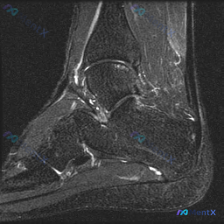

今天遇到一个挺有意思的病例,用户提示存在半月板异常,但只提供了单张膝关节MRI T1冠状位图像,整理一下分析思路分享给大家。 一、病例/影像基本信息 提供的单张膝关节MRI T1冠状位图像分析结果如下: 1. 骨骼结构:股骨远端、胫骨近端、腓骨近端轮廓清晰,骨髓信号正常,未见局灶性骨质破坏或异常信号...

今天整理一份很有代表性的膝关节MRI读片病例,和大家分享一下思路。这个病例最初是被怀疑有半月板异常,我们一起来看看实际情况。 病例影像基本信息 这是一份膝关节MRI冠状位T2加权图像,我们先梳理所有基础观察: 1. 股骨远端、胫骨近端骨髓信号正常,没有明显骨髓水肿 2. 半月板情况:内侧半月板体部形...